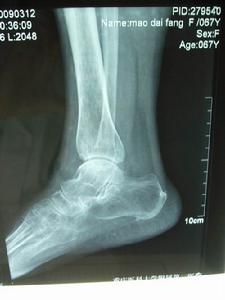

4.患者的膝关节、踝关节、髋关节和肩关节部位是很容易受到连累的,而手足关节和肘腕关节部位就比较少受累,但不是说不会发病。患者一旦出现以上症状表现,就要及时进行治疗,不能耽误了较佳治疗时间,否则,就会导致疾病进一步恶化,造成严重的后果。